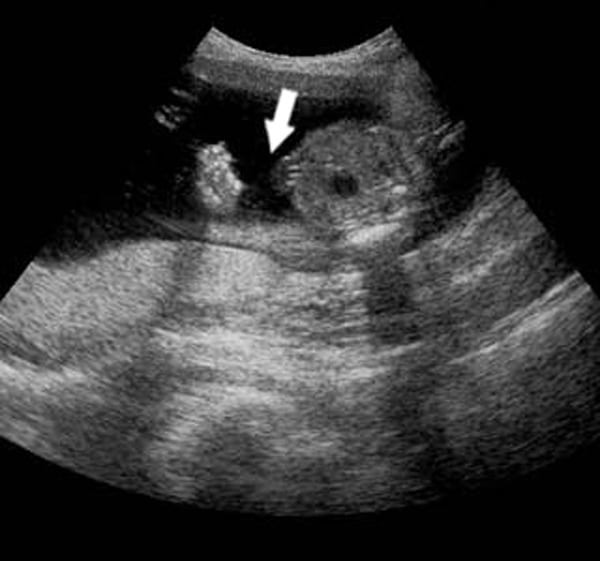

Thai nhi 11 tuần tuổi đã phát triển đầy đủ các ngũ quan trên khuôn mặt cũng như hình dáng tay, chân bên ngoài và các cơ quan thuộc hệ tiêu hóa, hệ bài tiết, hệ thần kinh... Đây là khoảng thời gian thích hợp cho mẹ bầu tiến hành siêu âm nhằm kiểm tra sức khỏe thai nhi toàn diện. Phương pháp này sẽ tiến hành đo độ mờ da gáy của thai nhi rồi dựa vào những số liệu thu thập được để phát hiện ra thai nhi có bị dị tật bẩm sinh hay không.

Nếu kết quả thu được cho biết chỉ số mờ da gáy của thai nhi 11 tuần là 2mm, điều đó có nghĩa thai nhi khỏe mạnh bình thường và không bị dị tật. Tuy nhiên, nếu con số này tăng lên hoặc giảm đi, em bé khi sinh ra có nguy cơ bị dị tật cao với một số bệnh thường gặp như bệnh down, hở hàm ếch... Mẹ bầu cần lưu ý tiến hành siêu âm đúng thời điểm, thường là từ tuần thứ 11 đến tuần thứ 14 để phát hiện dị tật sớm nhất và có hướng điều trị hiệu quả.

Mẹ cũng cần lưu ý rằng, độ mờ da gáy chỉ giúp bác sĩ phán đoán được 75% nguy cơ trẻ bị Down. Để đảm bảo kết quả chính xác hơn, mẹ cần làm thêm nhiều xét nghiệm chuyên sâu khác theo sự hướng dẫn của bác sĩ chuyên môn.